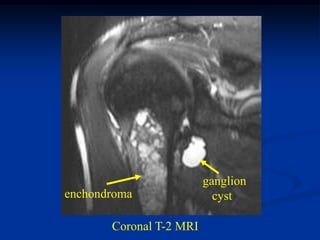

Case #554.1           Enchondroma and ganglion cyst

47 year male with shoulder pain for 6 months

ganglion

enchondroma                cyst

Coronal T-2 MRI

Sagittal T-2 enchondroma   Sagittal T-2 ganglion

Two different T-2 axial cuts showing the enchondroma

and the right cut shows the ganglion